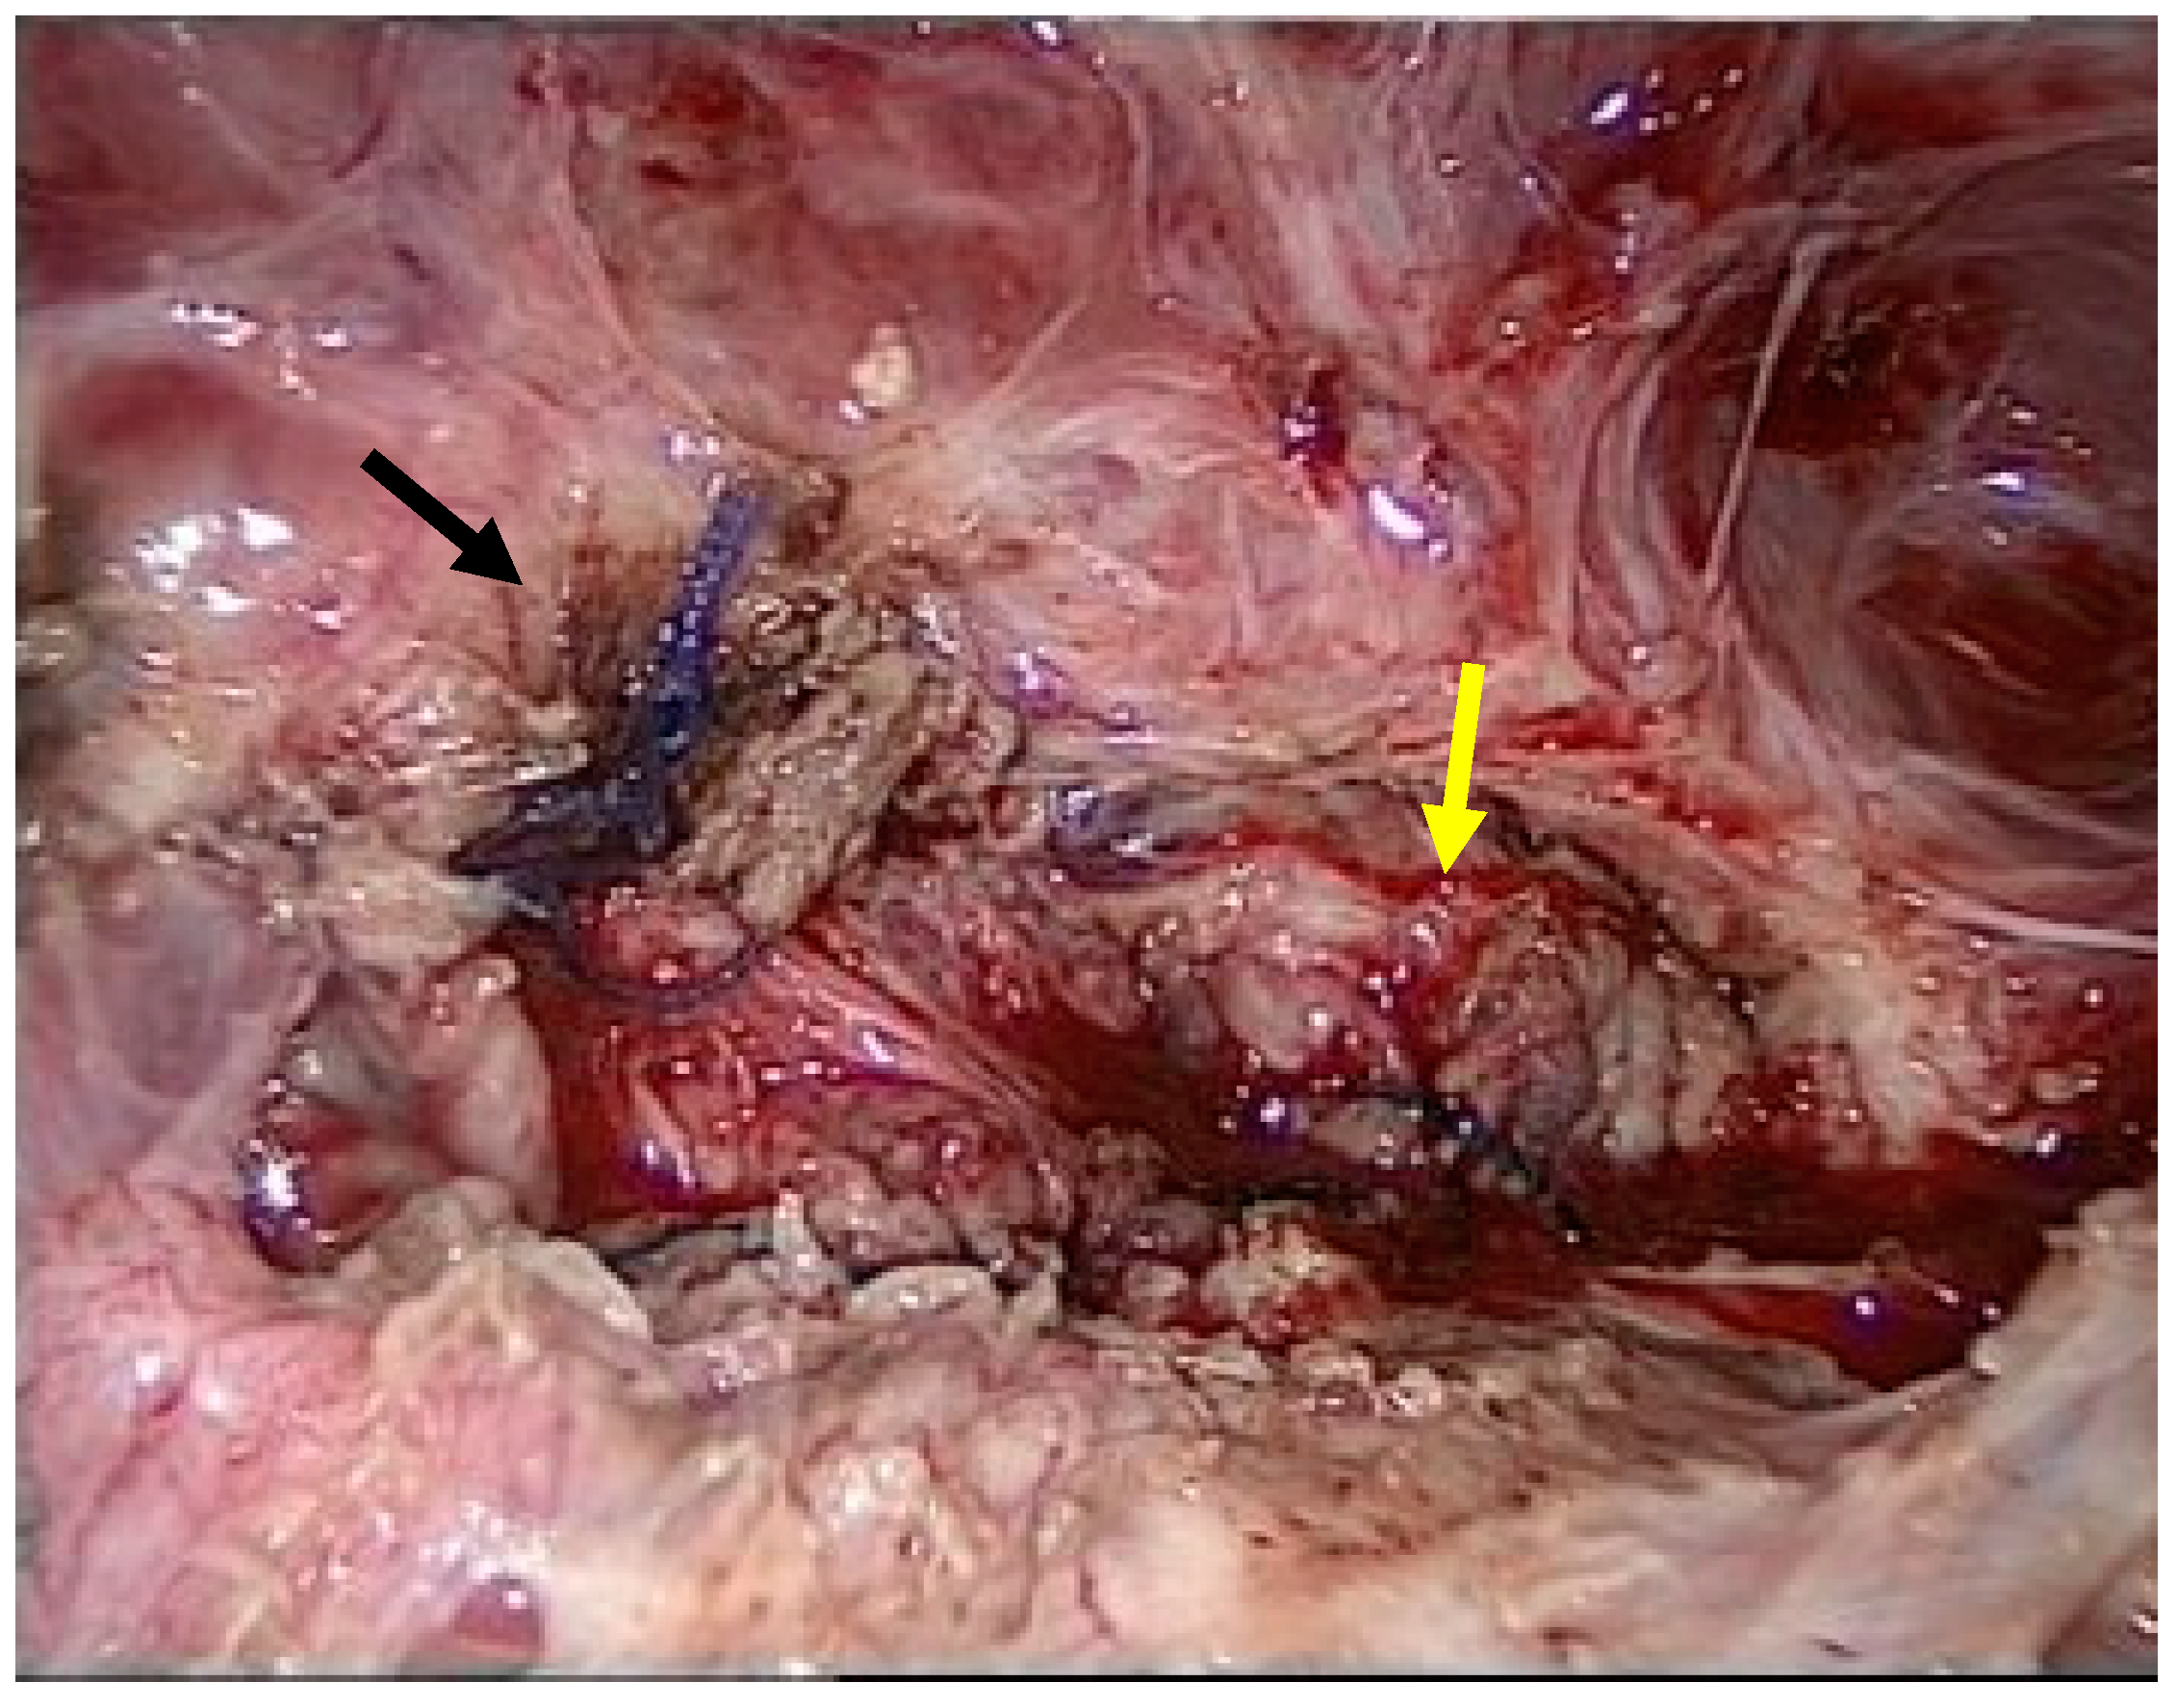

Due to the high symptom burden, the patient underwent surgery under general anesthesia via a minimally invasive laparoscopic approach. First, significant adhesions were observed between the urinary bladder and uterine body (Figure 2).

Figure 2.

Adhesion between the bladder and uterus (black arrow).